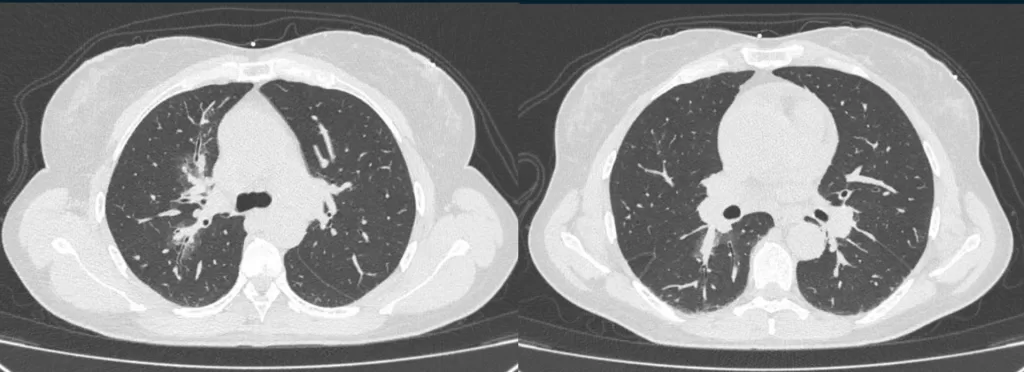

Tomografia Computadorizada de Tórax Sem Contraste

Janela Pulmonar